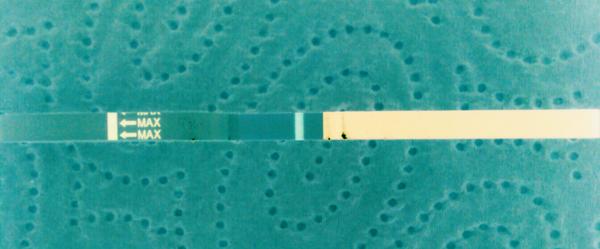

Těhotenský test. Dávám fotku. Co myslíte?

dnes jsem si dělala testík...

Udělal jsem radši ještě jeden - jmenuje se ForYou... Tam se objevil slabý duch, ale až tak za 3minuty! Šla jsem ven se psi a když jsem se vrátila, tak duch byl silnější...no ale to bylo skoro po půl hodině!

Tak nevim ... ☹ Dávám fotku, skuste posoudit...

@laura1972 zlati to ani nevim..protoze mam pocit,ze posl.mes.neovoluju..posl.ms mi dokonce prisla po 20dnech..proto jsem to zacala resit s dr..normalni foto nemam..protoze jsem mela pocit,ze to co tam vidim je klam..tak jsem to vyfotila rovnou v negativu..u me v tel.je to videt lip nez tady.